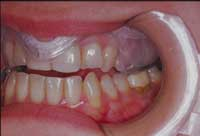

La maggior pressione da un lato farà defluire il liquido su quello opposto innescando un meccanismo di feedback (Foto 3) che tenderà in pochi minuti alla normalizzazione dei muscoli interessati. In pratica i due cuscinetti ricreano quell’appoggio indispensabile alla normalizzazione del sistema neuromuscolare. Il Paziente, da solo, utilizzando le sue funzioni riflesse, in modo involontario, a poco a poco si posiziona in una zona di equilibrio. Queste placche, davvero geniali, avevano il difetto di essere molto indaginose da realizzare. Ora, grazie al sistema Aqualizer®, tutto ciò è superato, in quanto sono state realizzate delle pseudoplacche preformate in tre misure che si adattano praticamente a tutte le arcate dentarie, a patto naturalmente che siano presenti elementi dentali sufficienti. (Foto 1 e 2)